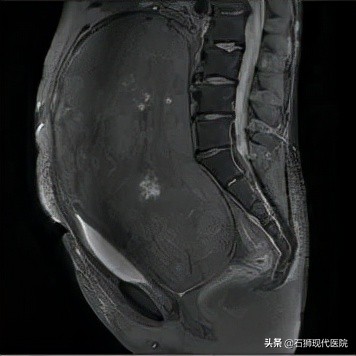

50岁女性患者,因频繁出现尿频,排尿困难并伴腰痛、发热至我院就诊。检查后诊断为宫颈来源的盆腔巨大肿块,肌瘤可能,伴有急性肾盂肾炎、左侧输尿管扩张、肾积水、高血压病、肝脏多发血管瘤。转入妇科病房。

入院后,妇科主任带领团队仔细了解患者病史,认为患者盆腔肿块巨大,填塞整个盆腔,已严重压迫左侧输尿管、膀胱颈部造成肾积水、急性肾盂肾炎、输尿管积水,如果不及时处理,可能造成更严重的脏器损害。但手术也面临极大的风险,其中包括术中大出血、输尿管损伤、肠管损伤、术后严重感染及肿块取出后因回心血量不足突发心衰等难题。团队与血管外科,麻醉科等多学科讨论后,决定使用术前髂内动脉球囊间歇性血流阻断及麻醉后手术前合理扩充血容量等措施,尽力减少术中出血,确保病人安全。手术切除的肿块最大径约30cm,重达4kg。全程历时2小时余,经病理冰冻检查肿块为宫颈来源的子宫平滑肌瘤。术中出血明显减少,手术过程顺利。这种血管间歇性血流阻断减少术中出血的方法为我院妇科首次开展,取得良好效果。术后患者恢复好,经复查左肾已恢复至轻度积水,双侧输尿管无扩张,排尿恢复正常出院。